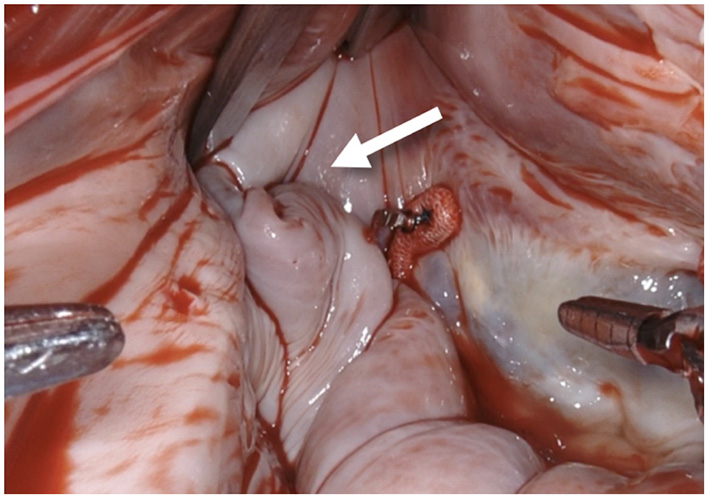

Figure 1

After performing a mitral valve repair, the entrance to the left atrial appendage (arrow) is exposed by using the atrial retractor, as seen on the upper edge.